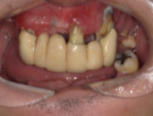

インプラントの症例紹介②

Before

After

主訴

歯がグラグラして噛めない

治療内容

上顎に対するインプラント治療を行った。

治療費

2,046,000円(税込)

治療期間

1か月

通院回数

3回

※治療回数は1回

想定されたリスク

※最終的な歯が入るまでは仮歯となりました。

One Dayインプラントなら、当日に仮歯が入り、すぐに噛めます。入れ歯の必要がなく、治療期間中も快適に過ごせる新しい選択肢です。